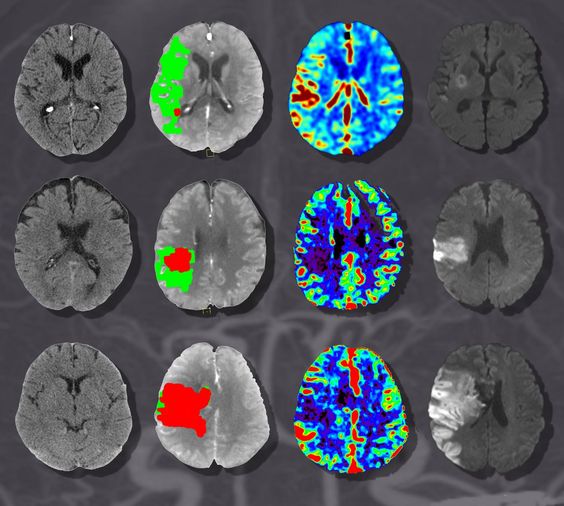

В настоящее время цереброваскулярные поражения, такие как атеросклероз, тромбозные окклюзии и стенозы являются одними из основных жизнеугрожающих состояний. Наиболее частым последствием стеноза артерий головного мозга является ишемический инсульт с последующим инфарктом мозговой ткани. Компьютерная томография в диагностике данной патологии получила наибольшее распространение среди остальных средств нейровизуализации. Однако обычная КТ не позволяла оценить перфузию ткани мозга и определить причину инфаркта. Поэтому её стали проводить с внутривенным введением контрастного вещества и метод стал называться КТ-ангиографией. Доступность исследования позволяет полностью отказаться от традиционной рентгеновской ангиографии и имеет ряд преимуществ перед МР-ангиографией.

КТ сосудов головного мозга показывает как просвет, так и стенки сосудов, что даёт возможность оценить стабильность атеросклеротической бляшки. Также в её возможности входит оценка васкуляризации опухоли, выявление её взаимоотношения с артериальными, венозными стволами и ликворной системой, изучение аневризматического мешка при субарахноидальном кровоизлиянии, положения стента после эндоваскулярного лечения, его проходимость и состояние интимы сосуда над ним.

В отличии от МР-ангиографии, во время которой обнаруженная атеросклеротическая бляшка проявляется потерей МР-сигнала, а, следовательно, невозможно исследовать состояние васкулярной стенки, по данным КТ-ангиографии можно выявить минимальный размер просвета стенозированного сосуда и даже характер бляшки- фиброзный, кальцинированный или же смешанный.

- проводится реконструкция полученных изображений в проекции максимальной интенсивности (MIP) в трех плоскостях для исследования сосудов, в проекции мультипланарной реконструкции (MPR) для обнаружения атеросклеротических бляшек и участков вазоспазма, также проводится 3D-реконструкция сосудов Виллизиевого круга.

КТ ангиография позволяет комплексно обследовать артерии и вены головного мозга с использованием рентгеновских лучей. Благодаря этому методу диагностики стало реально определить заболевания кровеносных сосудов, а так же проверить их функциональность и морфологию.